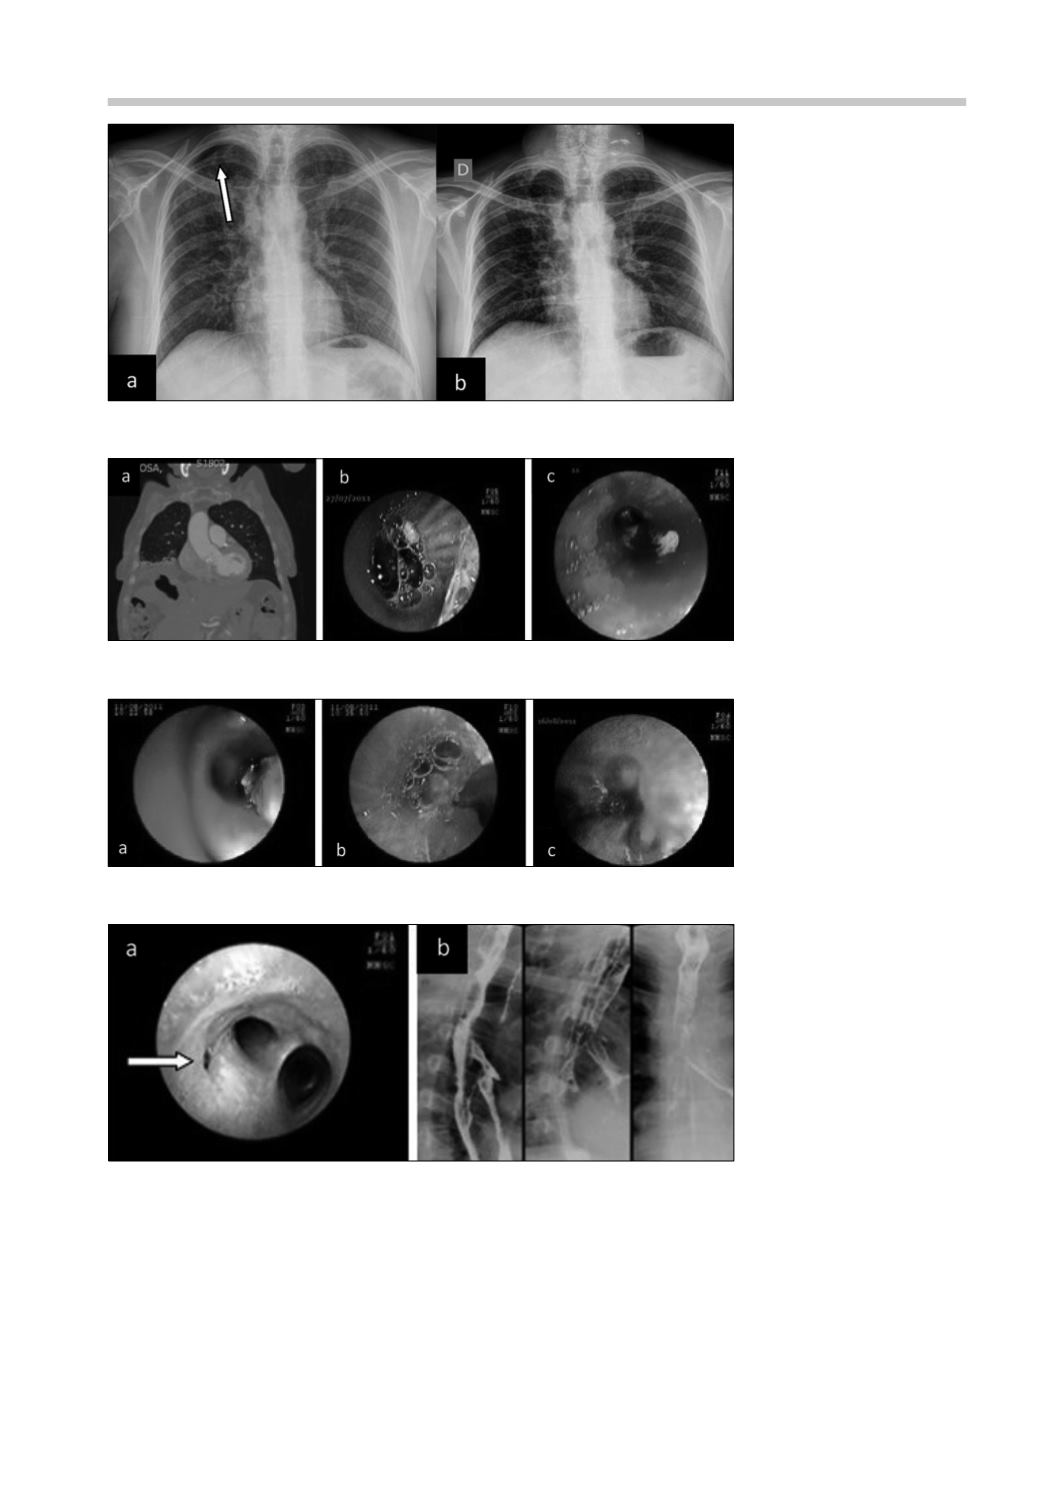

Figura 4.

Radiografías de tó-

rax.

a:

persiste neumotórax al

30º día (flecha);

b:

Resultado

al tercer día de la aplicación

de PRP: expansión completa

del pulmón derecho.

Figura 5.

Fístula hepato-pul-

monar.

TAC: comunicación

hepatopulmonar;

Imagen

broncoscópica: flujo de bilis

desde lóbulo medio;

c:

broncoscópica de membranas

hidatídicas.

Figura 6. a:

inyección de

etanol absoluto;

instilación

de PRP;

fístula sellada al 7°

día de PRP.

Figura 7.

Fístula esófago-

traqueal.

imagen broncos-

cópica muestra orificio fistu-

loso sobre la carina (flecha);

estudio radiológico: paso

del medio de contraste desde

el esófago a la tráquea.